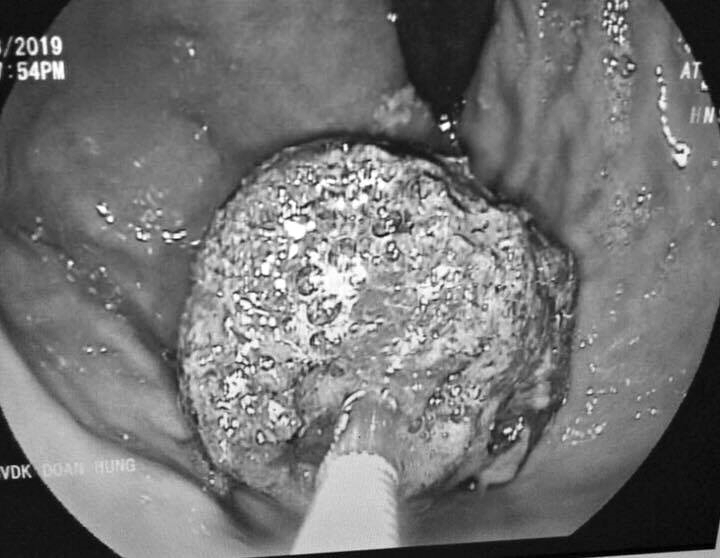

Tuy nhiên, sau khoảng 5 ngày điều trị, tình trạng bệnh không thuyên giảm, anh L. tiếp tục được chuyển lên Bệnh viện Đa khoa tỉnh Phú Thọ.Tại đây, kết quả chụp cắt lớp cho thấy, bệnh nhân bị tắc ruột do bã, quai ruột giãn to. Để điều trị, người bệnh được chỉ định phẫu thuật mở ruột, mở dạ dày lấy bã thức ăn.

Quá trình mổ các bác sĩ đã lấy ra 2 khối bã thức ăn lớn trong dạ dày và ruột non bệnh nhân. Hiện tại, tình trạng bệnh nhân dần ổn định và đang tiếp tục theo dõi sức khỏe tại bệnh viện.